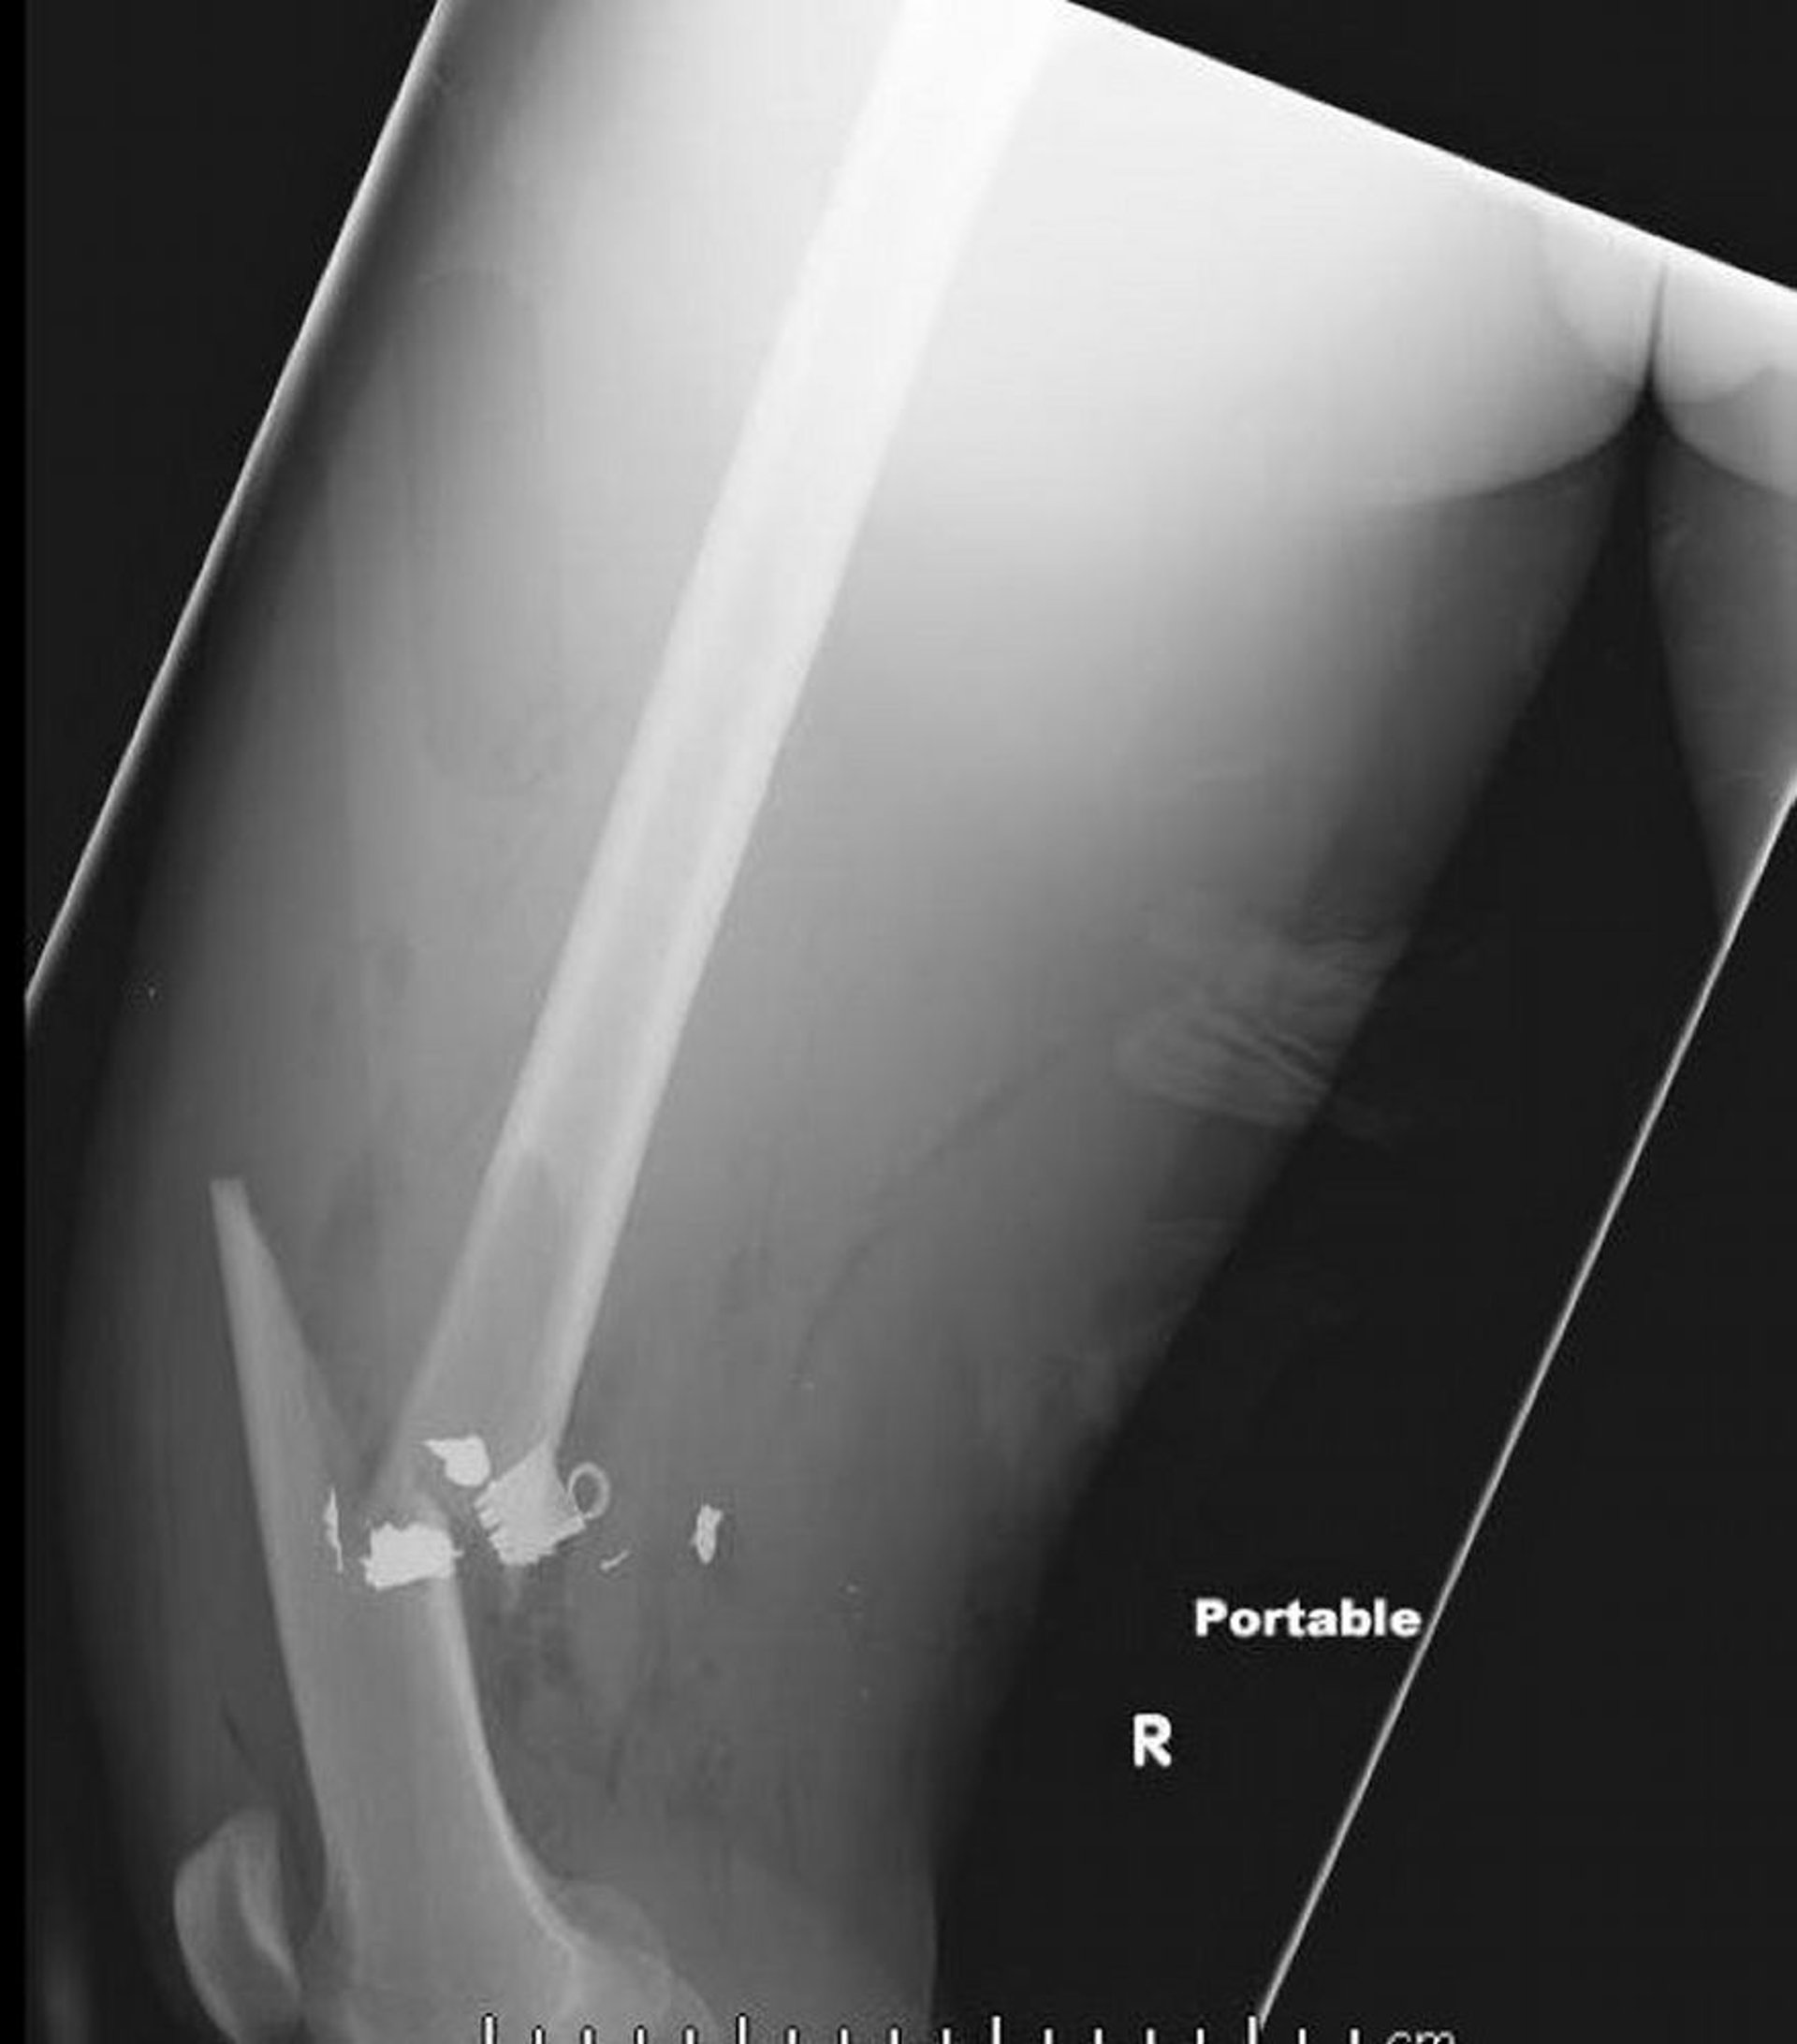

Перелом середньої частини стегнової кістки (2)

На даній рентгенограмі стегнової кістки в латеральній проекції показаний перелом стегнової кістки в її середній частині із наявністю повітря в м'яких тканинах і сторонніх металевих предметів.

Знімок люб'язно надано лікарем Даніелем Кампаньє [Danielle Campagne], MD.